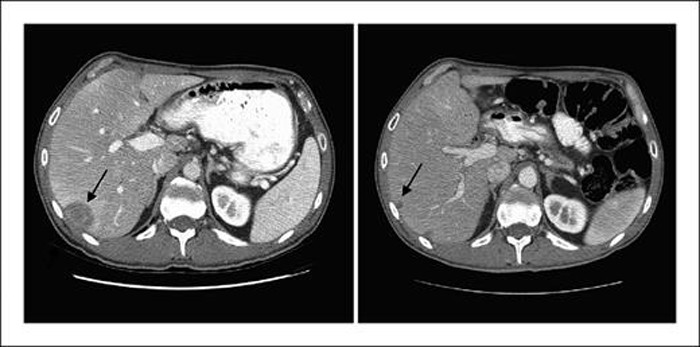

ThS. DS. Nguyễn Quế Hữu - Dược sĩ Đại học Dược Hà Nội dẫn chứng một số nghiên cứu, trong đó, thử nghiệm giai đoạn II về Curcumin ở bệnh nhân ung thư tuyến tụy tiến triển trong Nghiên cứu ung thư lâm sàng (2008) của Navneet Dhillon và cộng sự cho thấy sử dụng Curcumin giúp hỗ trợ làm giảm kích thước khối u.